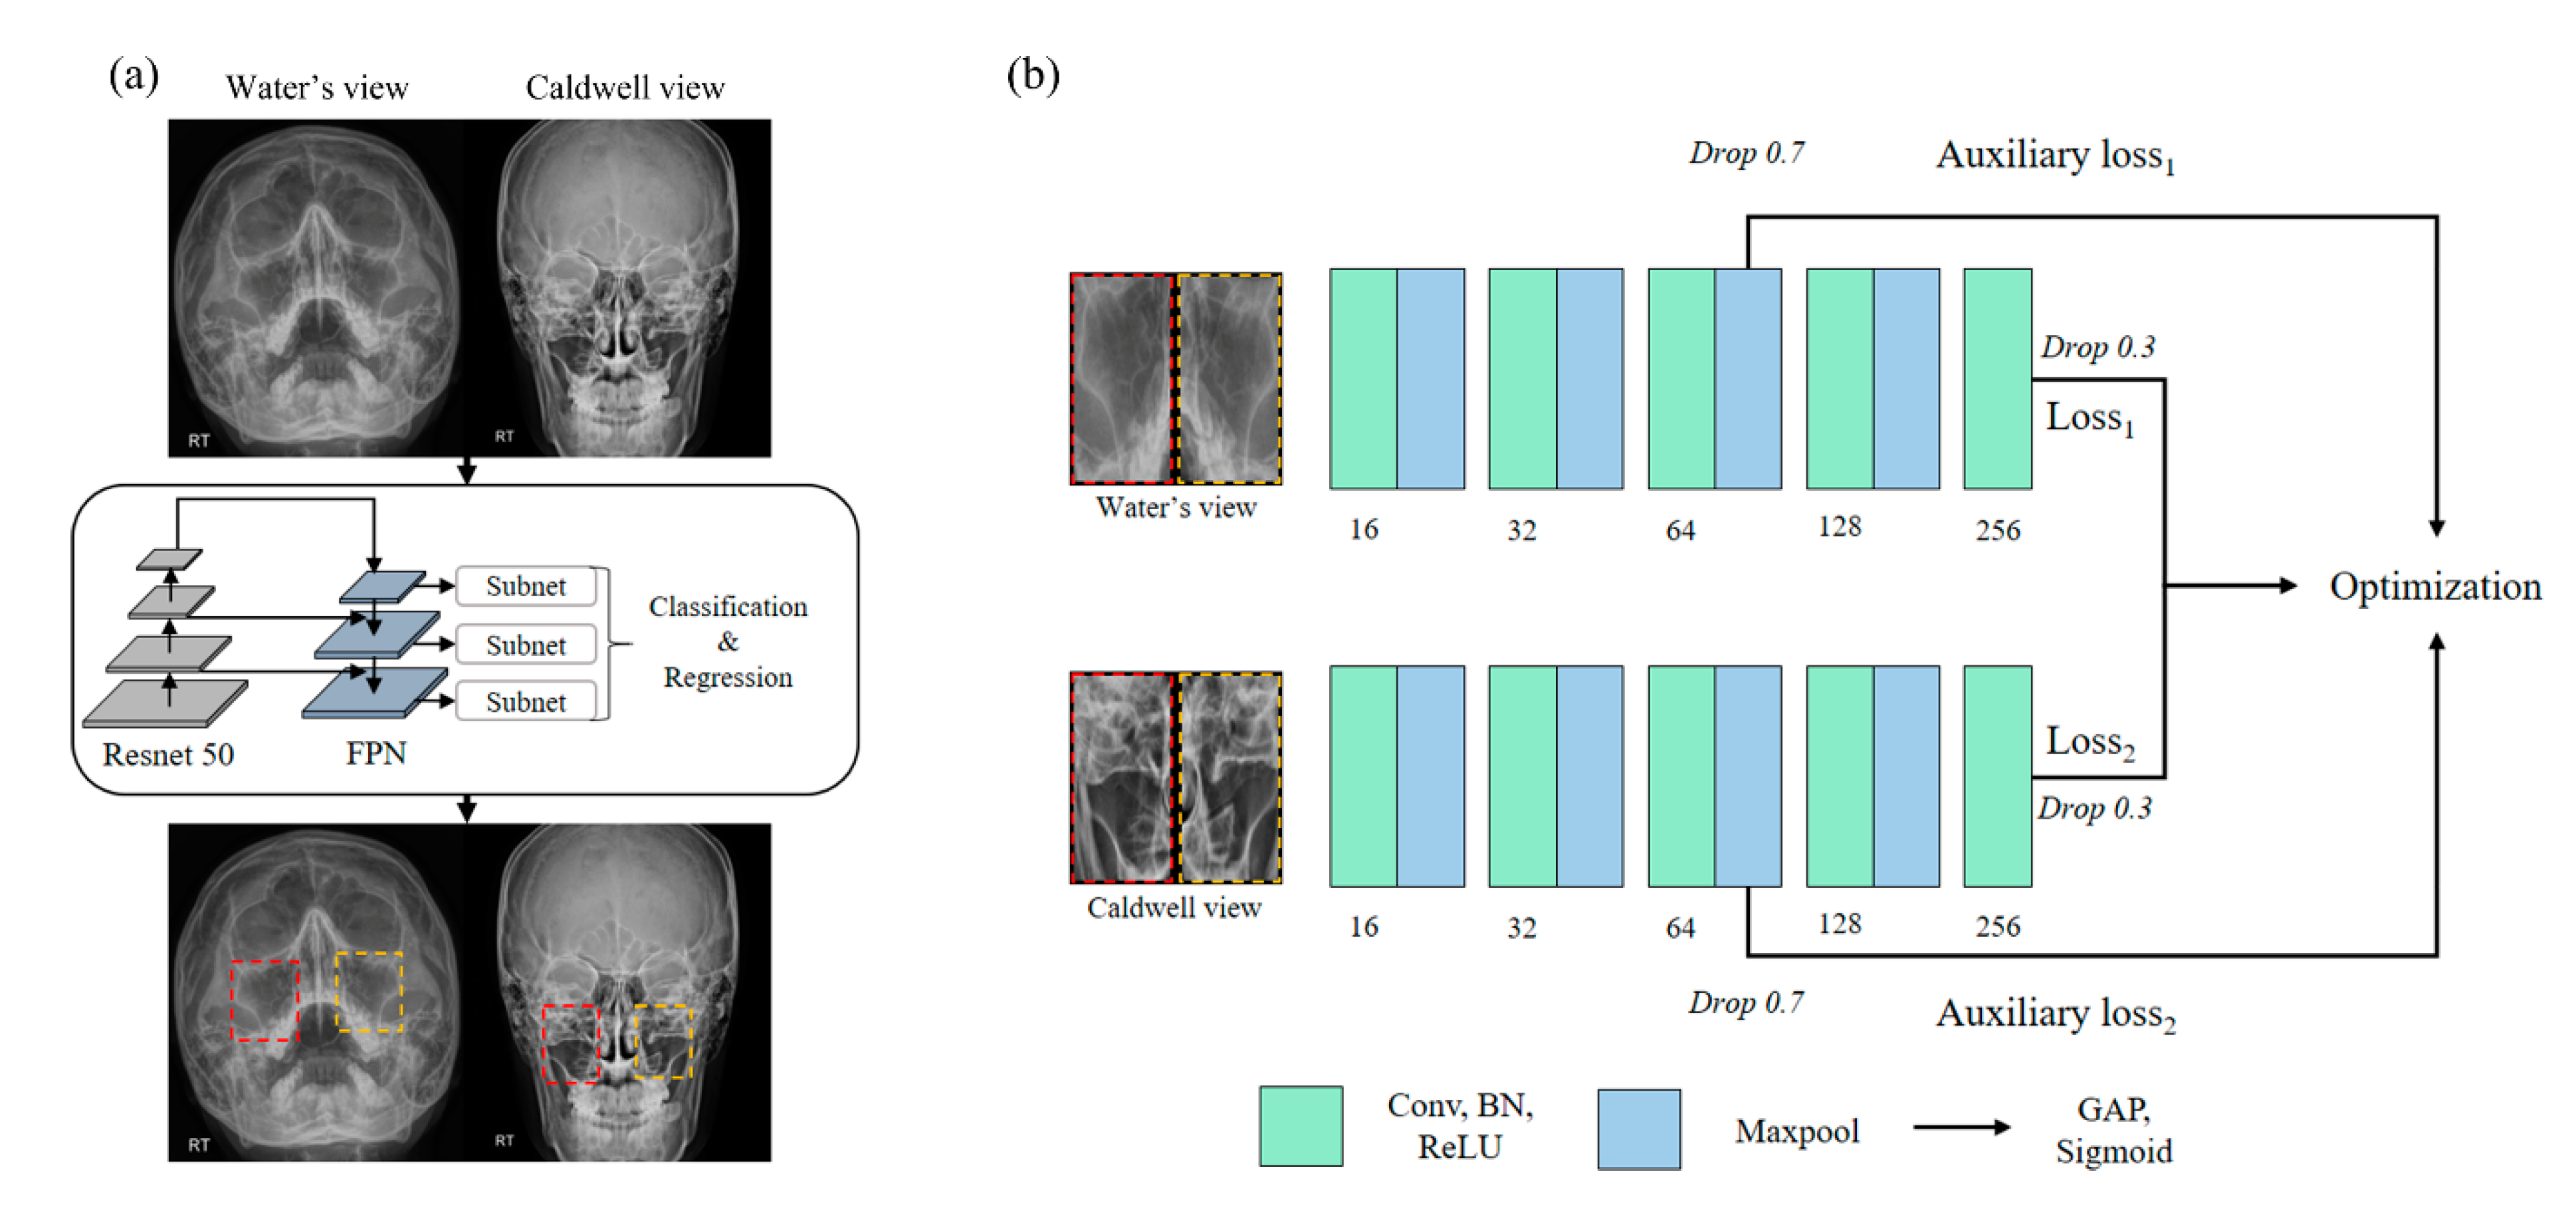

2.5. Region of Sinus Detection

2.6. Sinusitis Classification

3.1. Region of Sinus Detection